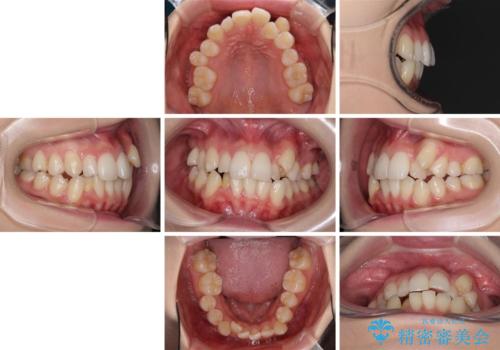

- 八重歯と奥歯の咬み合わせを気にして来院された患者様です。

インビザラインによる矯正治療を希望されたため、八重歯改善のための抜歯矯正部分は補助装置を併用し、その後はインビザラインにて行うこととしました。

下顎の右側変位が顕著であったため、ワイヤー矯正の方が咬み合わせは改善しやすいのですが、ある程度は時間がかかっても良いとのことであったので、インビザラインにて矯正治療を行うこととしました。

骨格的に下顎が右側に変位していたため、上下正中を合わせることは困難であることは分かっていました。それでも、なるべく合わせるようにとしたため、治療期間は長期間となりました。